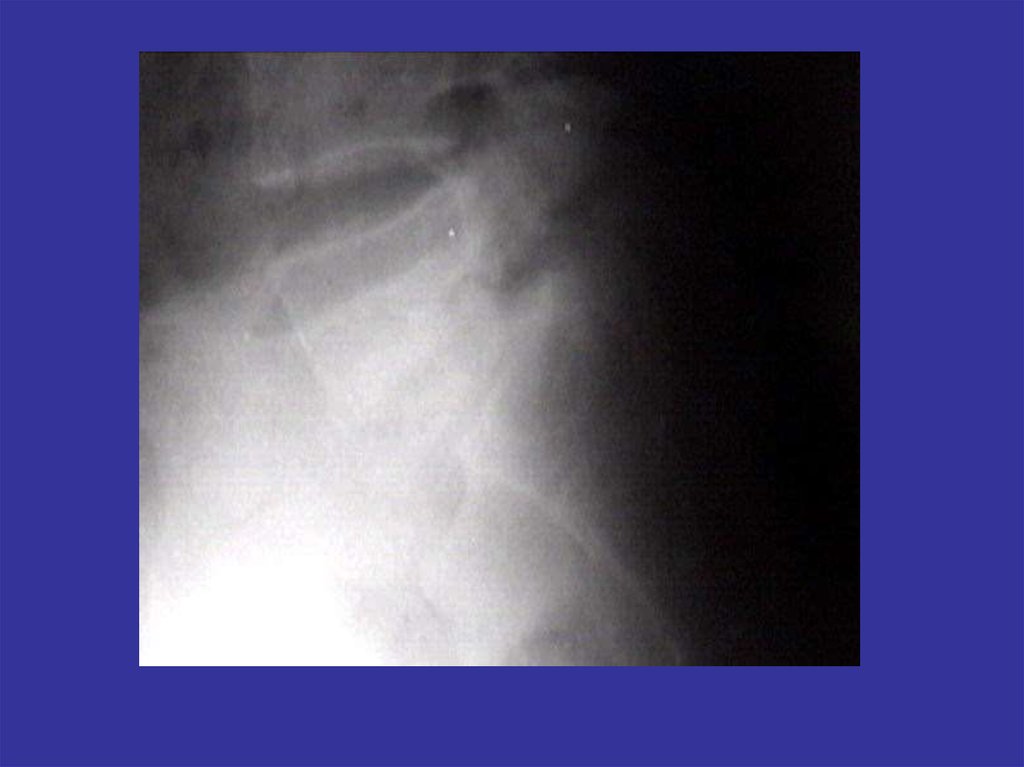

Аномалии развития позвоночника